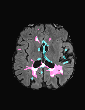

In recent years, data-driven machine learning (ML) methods have revolutionized the computer vision community by providing novel efficient solutions to many unsolved (medical) image analysis problems. However, due to the increasing privacy concerns and data fragmentation on many different sites, existing medical data are not fully utilized, thus limiting the potential of ML. Federated learning (FL) enables multiple parties to collaboratively train a ML model without exchanging local data. However, data heterogeneity (non-IID) among the distributed clients is yet a challenge. To this end, we propose a novel federated method, denoted Federated Disentanglement (FedDis), to disentangle the parameter space into shape and appearance, and only share the shape parameter with the clients. FedDis is based on the assumption that the anatomical structure in brain MRI images is similar across multiple institutions, and sharing the shape knowledge would be beneficial in anomaly detection. In this paper, we leverage healthy brain scans of 623 subjects from multiple sites with real data (OASIS, ADNI) in a privacy-preserving fashion to learn a model of normal anatomy, that allows to segment abnormal structures. We demonstrate a superior performance of FedDis on real pathological databases containing 109 subjects; two publicly available MS Lesions (MSLUB, MSISBI), and an in-house database with MS and Glioblastoma (MSI and GBI). FedDis achieved an average dice performance of 0.38, outperforming the state-of-the-art (SOTA) auto-encoder by 42% and the SOTA federated method by 11%. Further, we illustrate that FedDis learns a shape embedding that is orthogonal to the appearance and consistent under different intensity augmentations.